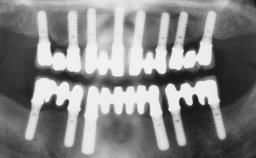

Conventional Loading of Eight Implants in the Maxilla and Final Restoration with a Full-Arch Gold-Ceramic FDP

# of Implants | 8 |